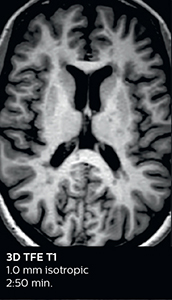

Fast MS protocol with optional sequences

The abbreviated MS protocol for brain is only around 9 minutes, so in case of suspected multiple sclerosis, one or two more advanced sequences may be added, such as PSIR (phase sensitive inversion recovery) or susceptibility-weighted sequences to help us make more confident diagnoses in these inflammatory cases.

3D TFE T1

3D FLAIR

DWI image

3D T1w TSE Gd

3D PSIR

3D SWI